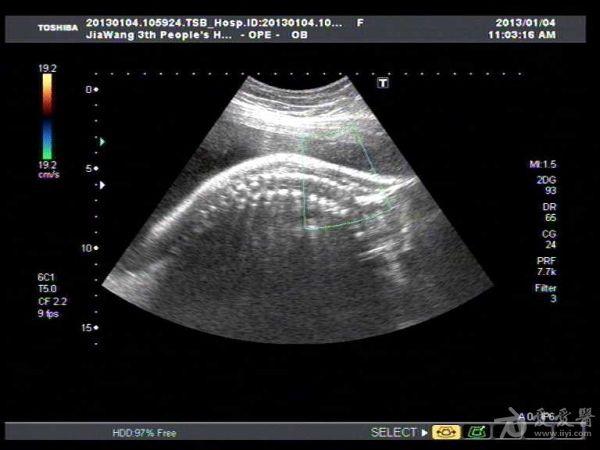

此孕妇听信家人说吃核桃能补脑,吃了两个月核桃来来复查,脑积水更明显。